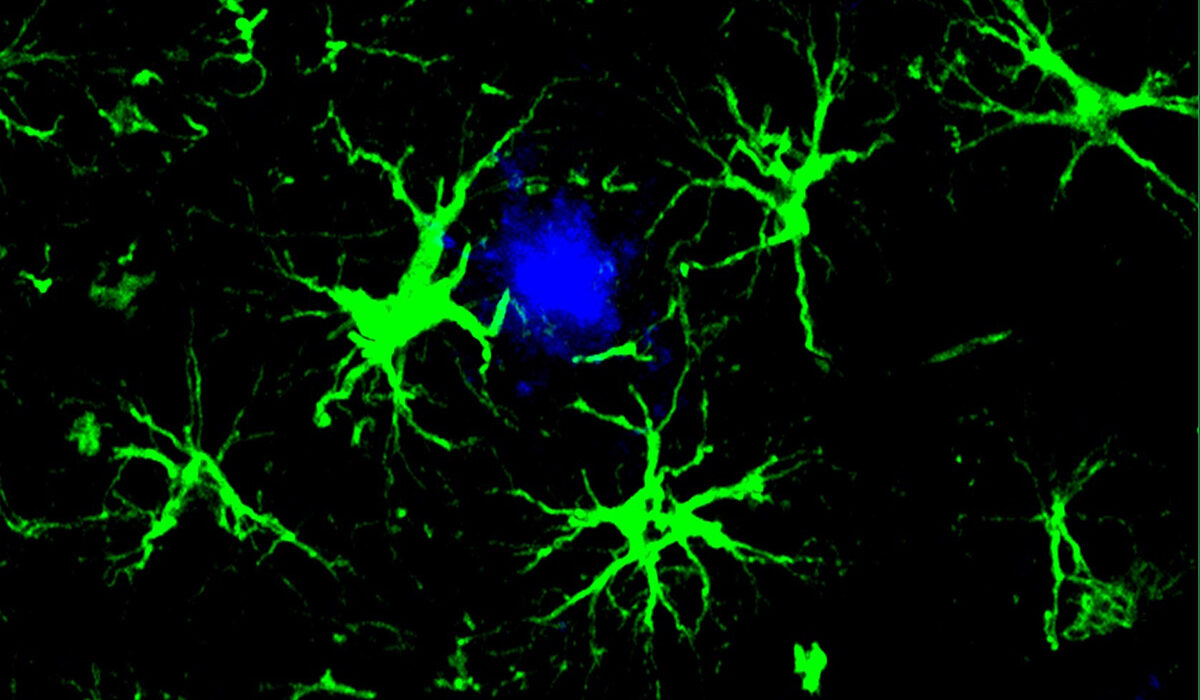

WashU Medicine researchers designed a cellular immunotherapy that turns astrocytes (green), a type of cell in the brain, into super cleaners that sweep away Alzheimer’s-related proteins. With this new feature, the cells successfully reduced the amount of harmful amyloid beta plaques (blue) in the brains of mice. (Image: Yun Chen/WashU Medicine)

Like CAR-T cell therapies used for cancer treatment, in which T cells of the immune system are genetically modified to attack cancer cells, this new approach equips cells — in this case, brain cells called astrocytes — with a CAR homing device to grab onto a target for destruction. These new CAR-astrocyte cells have features that transform them into super cleaners that remove damaging proteins from the brain that play a role in cognitive decline.

To reduce the cleaning burden on microglia, first author Yun Chen, PhD, then a graduate student in the labs of Colonna and David M. Holtzman, MD, the Barbara Burton and Reuben M. Morriss III Distinguished Professor of Neurology at WashU Medicine, transformed astrocytes, the most abundant cell type in the brain, into amyloid-cleaning machines. He custom-designed and delivered a gene to astrocytes that codes for the chimeric antigen receptor (CAR) via a harmless virus injected into mice. The CAR, now present on the surface of astrocytes, enabled the cells to capture and engulf amyloid beta proteins. With their newly acquired ability, the astrocytes — generally responsible for keeping the brain tidy — concentrated their efforts on only cleaning amyloid beta plaques in mice prone to its buildup.